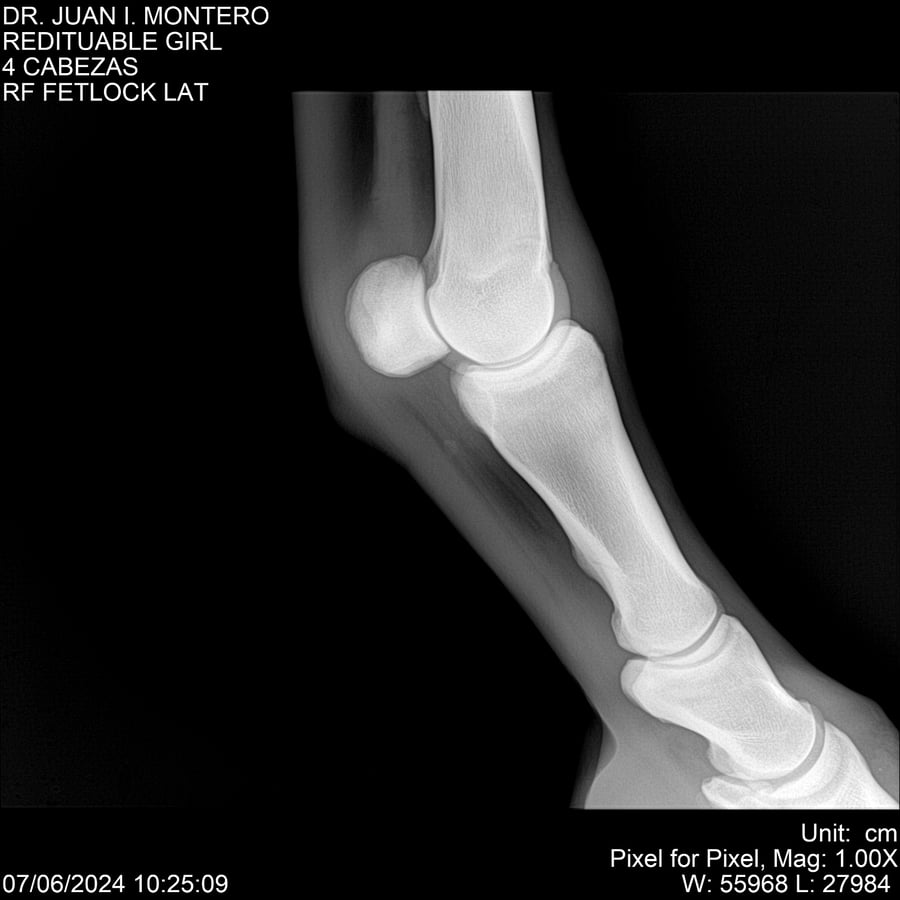

LOTE 19, REDITUABLE GIRL Lote Anterior Volver al remate Lote Siguiente Ficha Contacto Montevideo - Ficha del Lote Identificador: #281096 Categoría: Yeguarizos Montevideo - 79 Visualizaciones ClicData Contacto Empresa: Abelenda N. R., Walter Hugo Nombre*: Teléfono* : E-mail* : Mensaje Enviar Registrese gratis Este contenido Exclusivo está disponible sólo para usuarios registrados Ingresar